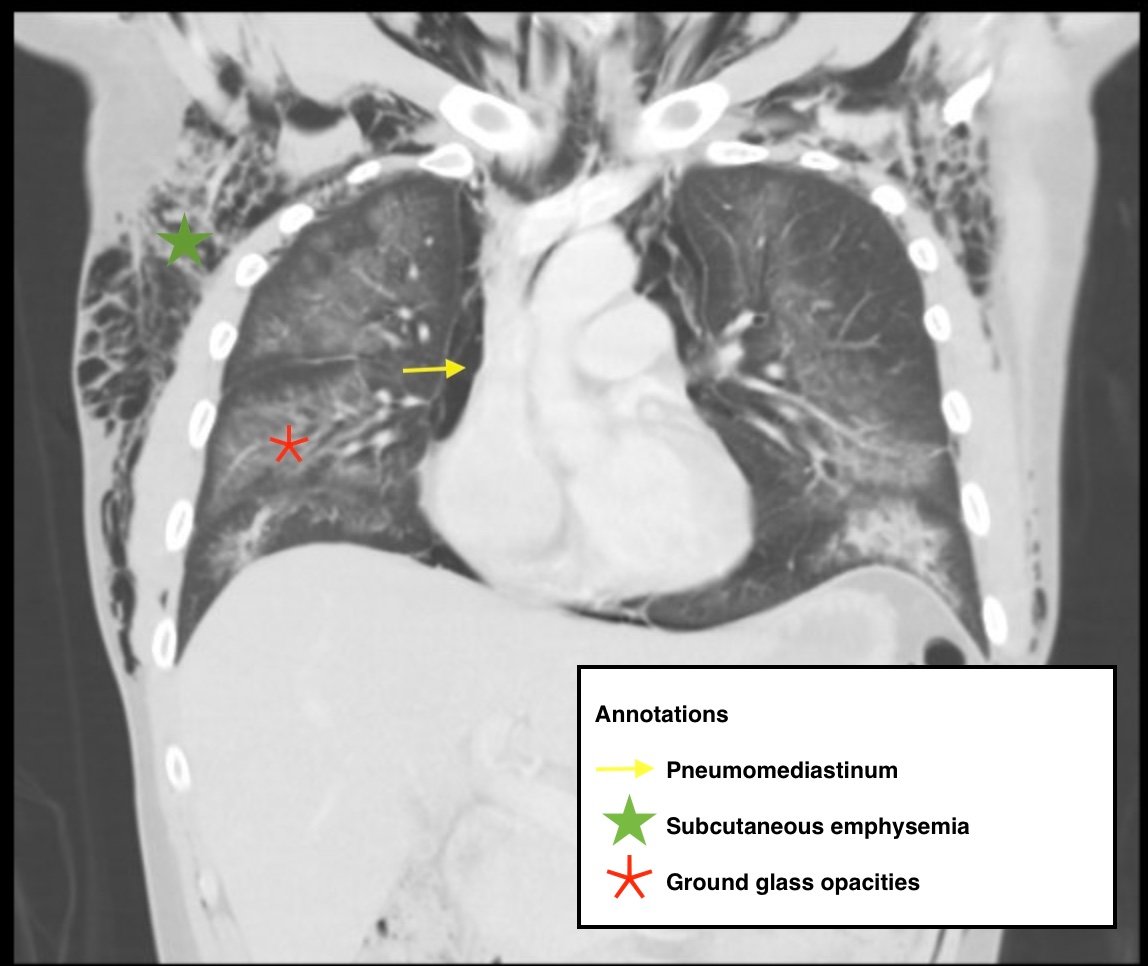

Electronic cigarette (e-cigarette) or vaping associated lung injury (EVALI) cases have increased with the popularity of e-cigarettes in the mostly young, healthy population. Some common symptoms associated with EVALI include shortness of breath and chest pain, and the most common diagnostic imaging findings are organizing pneumonia and diffuse alveolar damage seen on computed tomography (CT). Pneumomediastinum is a known sequela of EVALI.1 In the setting of pneumomediastinum in EVALI, EVALI is a diagnosis of exclusion, so other sources of pneumomediastinum need to be evaluated. EVALI has diverse presentations, and this case is a unique representation of a disease process that is becoming more commonplace with the increase in popularity of vaping. It is important to be aware of the clinical symptoms of EVALI, which can be nonspecific and can include gastrointestinal symptoms along with respiratory symptoms. It is equally important to recognize the diverse image findings of EVALI, which can include subcutaneous emphysema and pneumomediastinum. In this case, pneumomediastinum is seen in EVALI, and the patient was successfully treated with empiric antibiotic coverage, steroids, and conservative measures—making sure to limit any coughing or increases in intrathoracic pressure that can cause worsening of pneumomediastinum.

EVALI, vaping, pneumomediastinum, E-cigarette, ground-glass opacity.